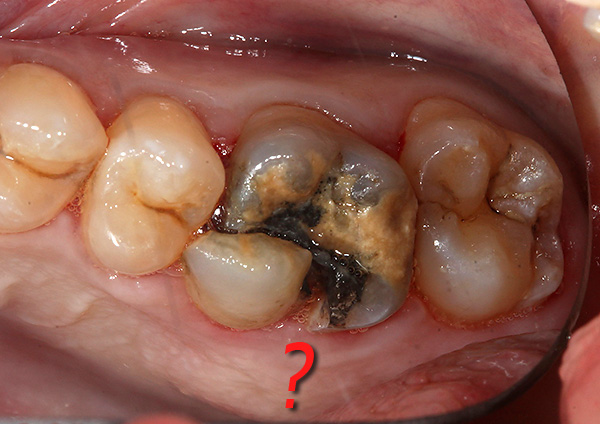

A fotografia abaixo mostra um exemplo de um dente serrado antes da remoção em três partes usando uma broca:

Nota

Um cirurgião-dentista nem sempre pode determinar com antecedência se a extração dentária será difícil ou simples. Em muitos casos, o médico pode adivinhar aproximadamente qual dente deve esperar dificuldades e qual quase saltará do buraco durante a remoção.

Às vezes, um especialista vê imediatamente um dente potencialmente complexo (resorcinol-formalina, semi-refinado, refinado, com raízes específicas) e avisa o paciente com antecedência que o procedimento será difícil e desconfortável.